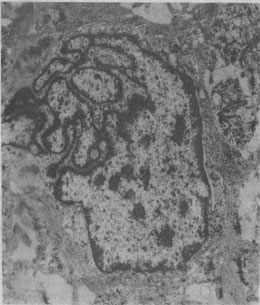

图1-1 恶性肿细胞的奇异形核

图中央为一巨大的细胞核,核膜曲折凹陷,使核呈奇异形(纤维肉的电镜照片)